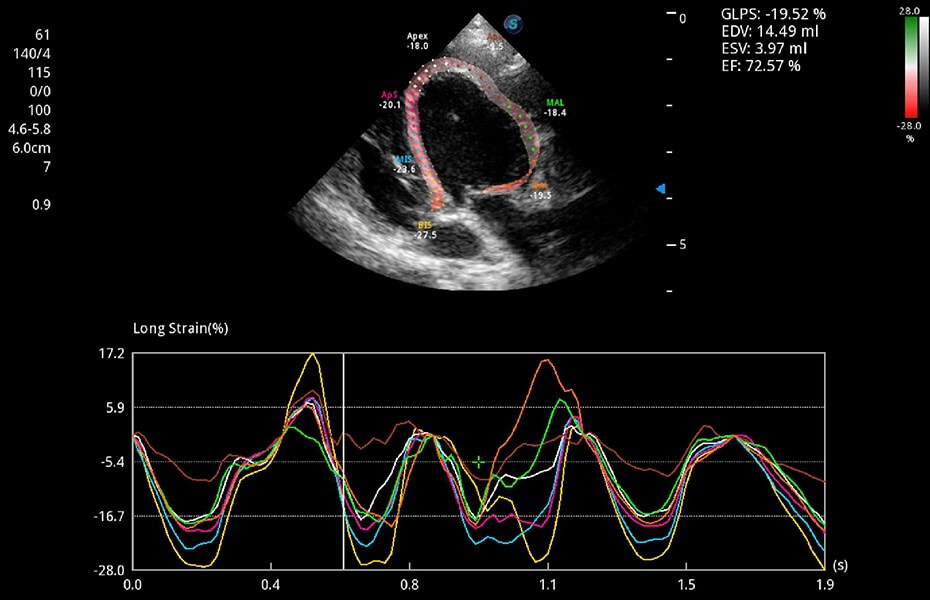

• MQA 心肌定量分析

通過(guò)心肌識(shí)別技術(shù)與二維斑點(diǎn)追蹤技術(shù)相結(jié)合,對(duì)心臟的超聲圖像進(jìn)行量化分析。計(jì)算心肌17個(gè)節(jié)段的應(yīng)變、應(yīng)變率、速度、位移等,并通過(guò)牛眼圖的形式進(jìn)行呈現(xiàn)。